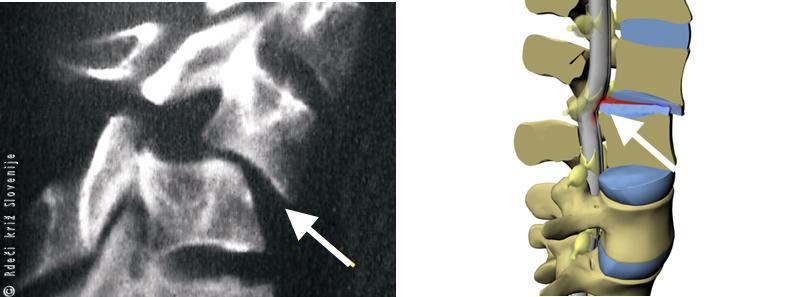

Slika 5

Vretence se lahko premakne nazaj, naprej ali vstran. Ob tem se pretrgajo medvretenčne ploščice in izpahnejo medvretenčni sklepi.

Slika 6

A – Najpogosteje se zlomi telo vretenca pri padcu na glavo ali zadnjico.

B – Kostni odlomki lahko poškodujejo hrbtenjačo.

Slika 7

Hrbtenjačo lahko poškodujejo kostni odlomki (A), medvretenčna ploščica (B), redkeje se zgodi, da se zaradi strižnih sil hrbtenjača nategne ali celo pretrga (C).